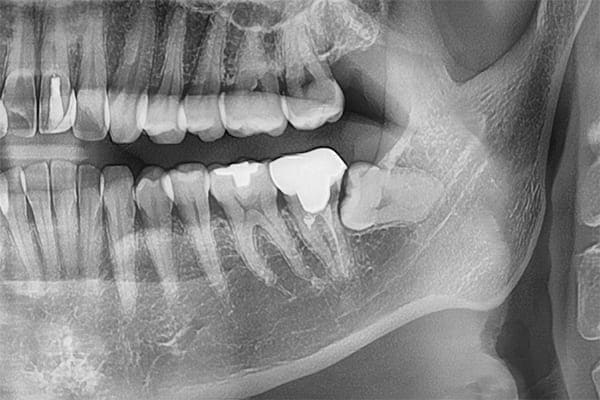

親知らず抜歯の症例ケース

歯ぐきの中で完全に真横に生えてしまうタイプです。

この親知らずを水平埋伏智歯と言います。

このタイプは、ほとんどが下顎のケースです。真横に生えているので、抜歯の際は難易度が高く2~3つに砕いて分けて抜歯をします。